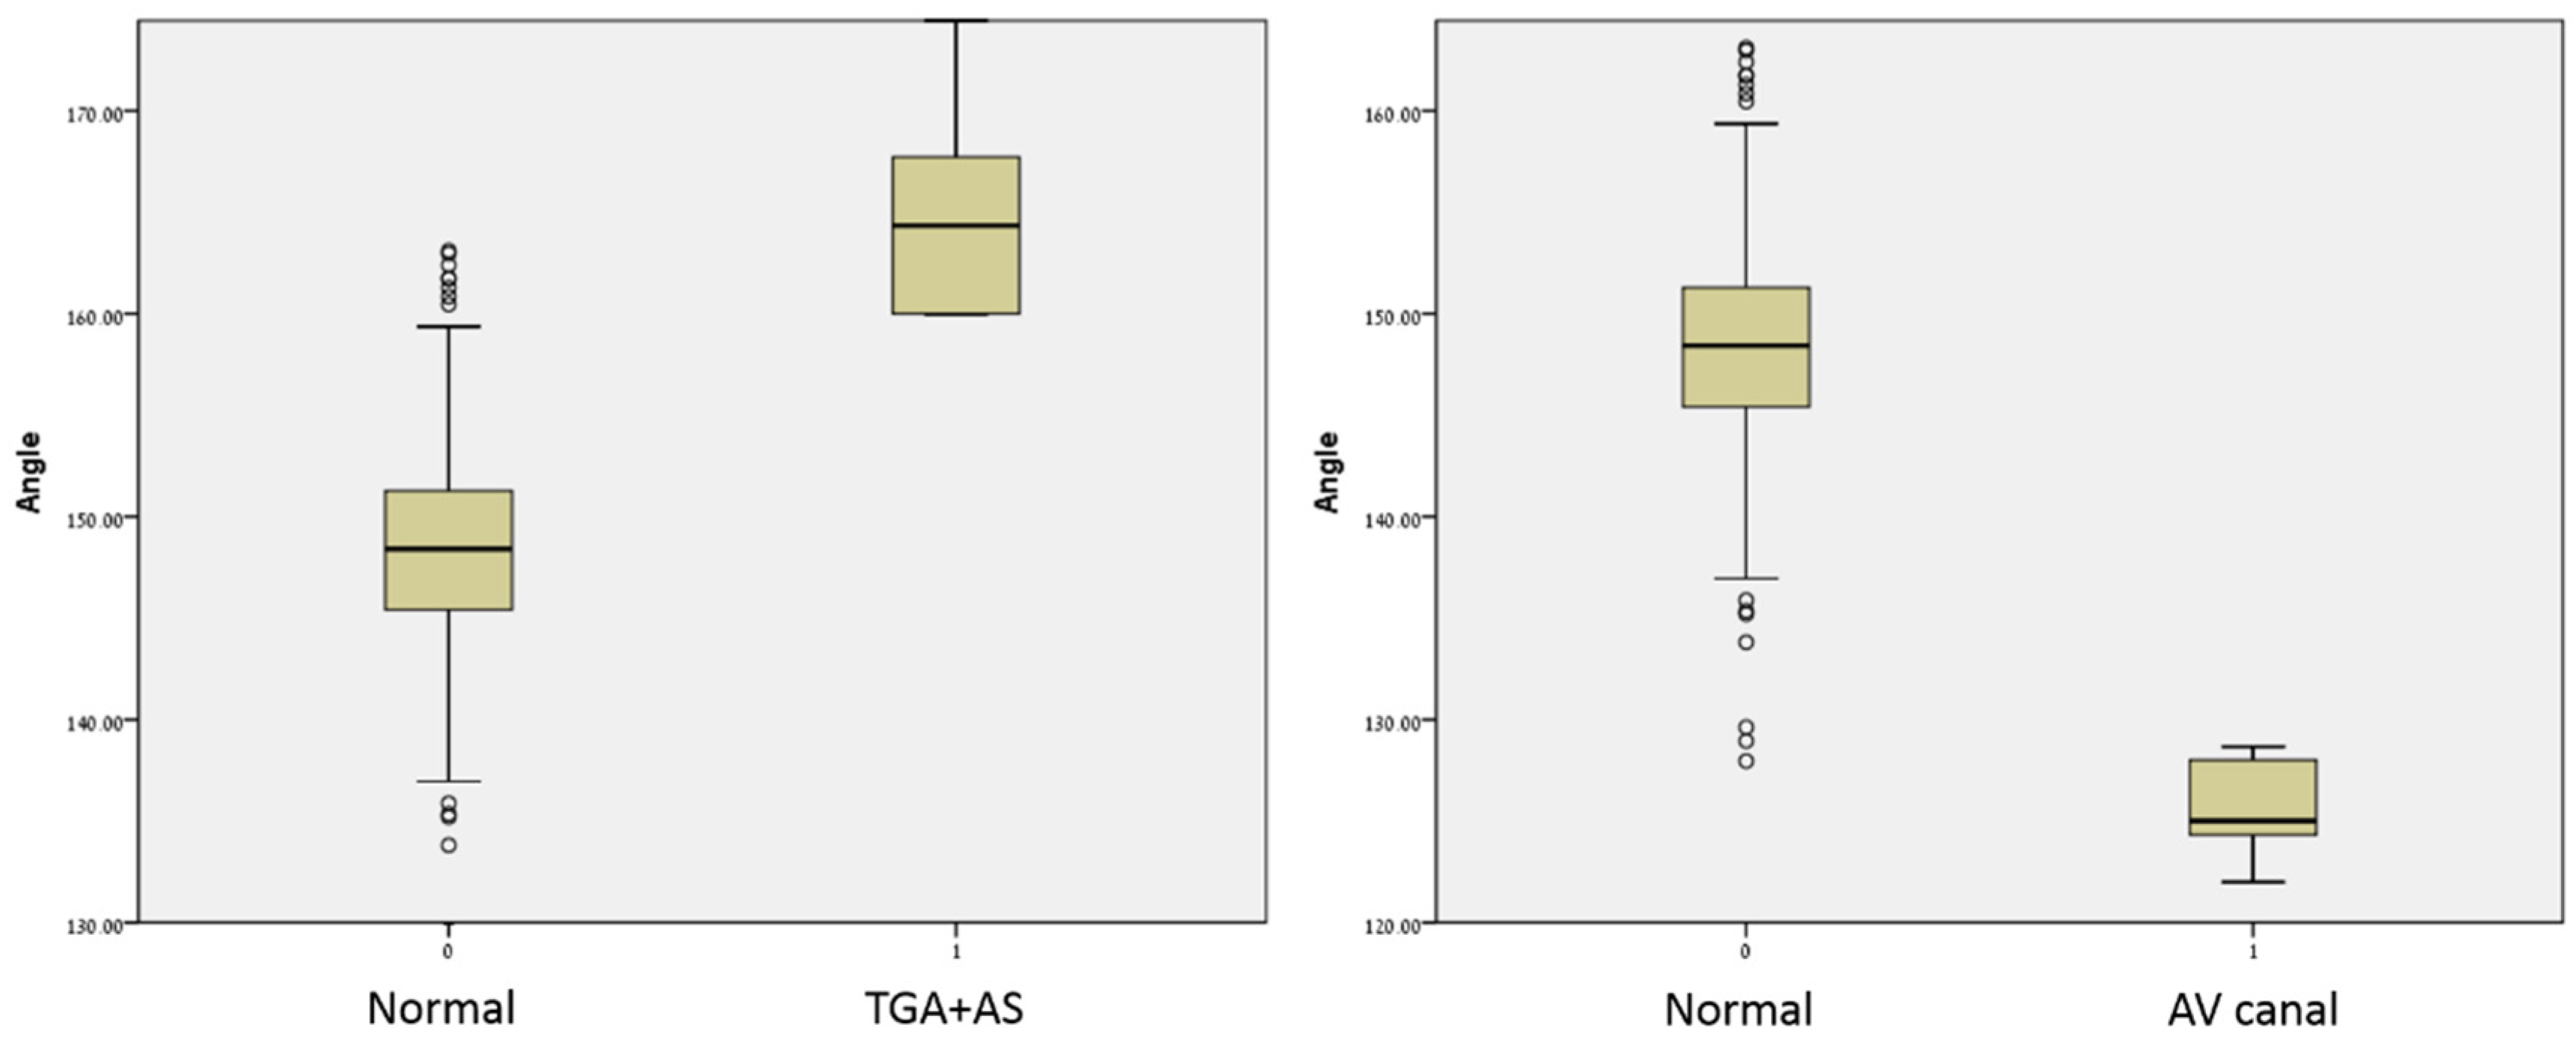

3. Results

| Fetuses with Normal Hearts (n = 293) | AVC (n = 8) | p-Value | TGA/AS (n = 11) | p-Value | |

|---|---|---|---|---|---|

| Angle | 148.2 ± 5.4 (127–163) | 124.8 ± 2.4 (122–128.6) | <0.001 | 164.8 ± 5.0 (159.9–175.2) | <0.001 |